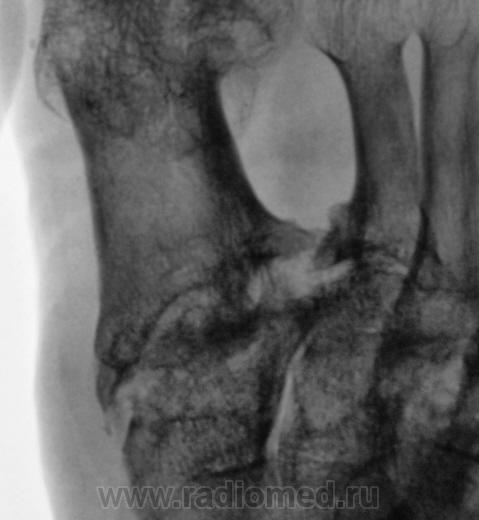

Пациентка направлена на рентгенографию стоп в прямой проекции с диагнохом - "Поперечное плоскостопие".

Произведена рентгенография обеих стоп в прямой проекции.

Думаю, что это дисхондроплазия - болезнь Олье.

Сильно сомневаюсь в болезни Олье - затронуты только суставные концы, диафизы интактны. Считаю - остеоартропатия, вероятнее всего - подагра

Классика подагры - наличие тофусов в параартикулярных мягких тканях... Механизм поражения скелета при подагре - атрофия от давления тофусами. А здесь - их совершенно не видно, мягкие ткани просто отодвинуты, но обьем то их - нормальный...

Согласен с артропатией, но подагра - сомнительно....

Поскольку артропатий великое множество....почему бы и не псориатическая...к примеру. Как там с анамнезом?

Пациентка весьма преклонного возраста - за 70 лет.